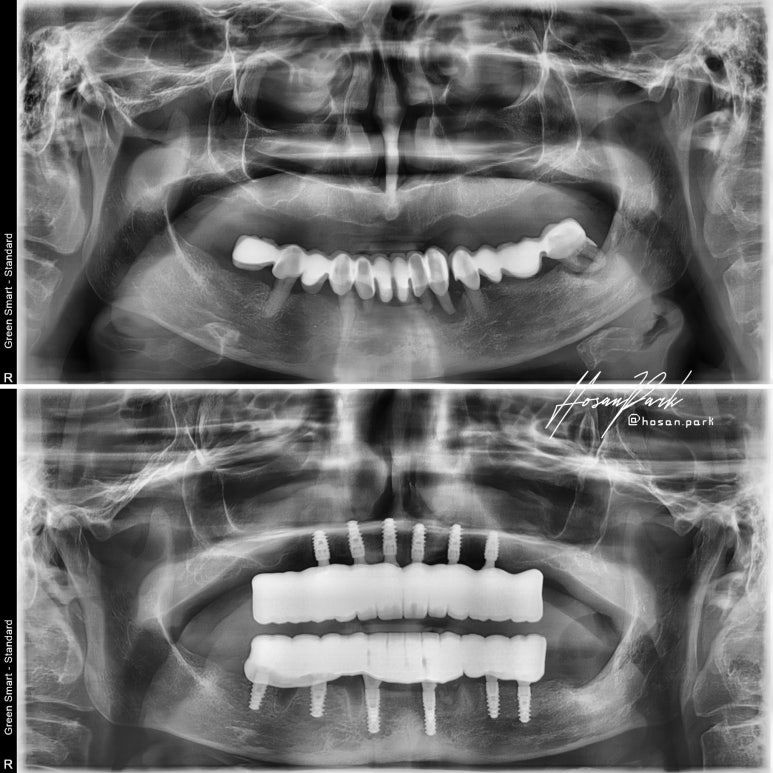

엑스레이 비교사진입니다.

상악은 의치, 소위 말해서 틀니 상태로 내원하셨고, 하악은 브릿지 상태였으나 남아있는 치아의 잇몸 상태가 좋지 않아 발치를 계획하게 되었답니다.

하여 상악에는 총 6개 임플란트, 하악에도 총 6개 임플란트를 심고, 국산과 외산 임플란트 중 장단점 설명을 들으시고 나서 저희 병원 시그니쳐 임플란트인 #스트라우만 BLX 임플란트로 결정하셨답니다.

상악 6개, 하악 6개 스트라우만 임플란트 식립

상악 및 하악에 총 12개의 임플란트를 식립하고 아래 3개의 치아는 고정성 임시치아를 만들어 드리기 위해 남겨두었답니다.